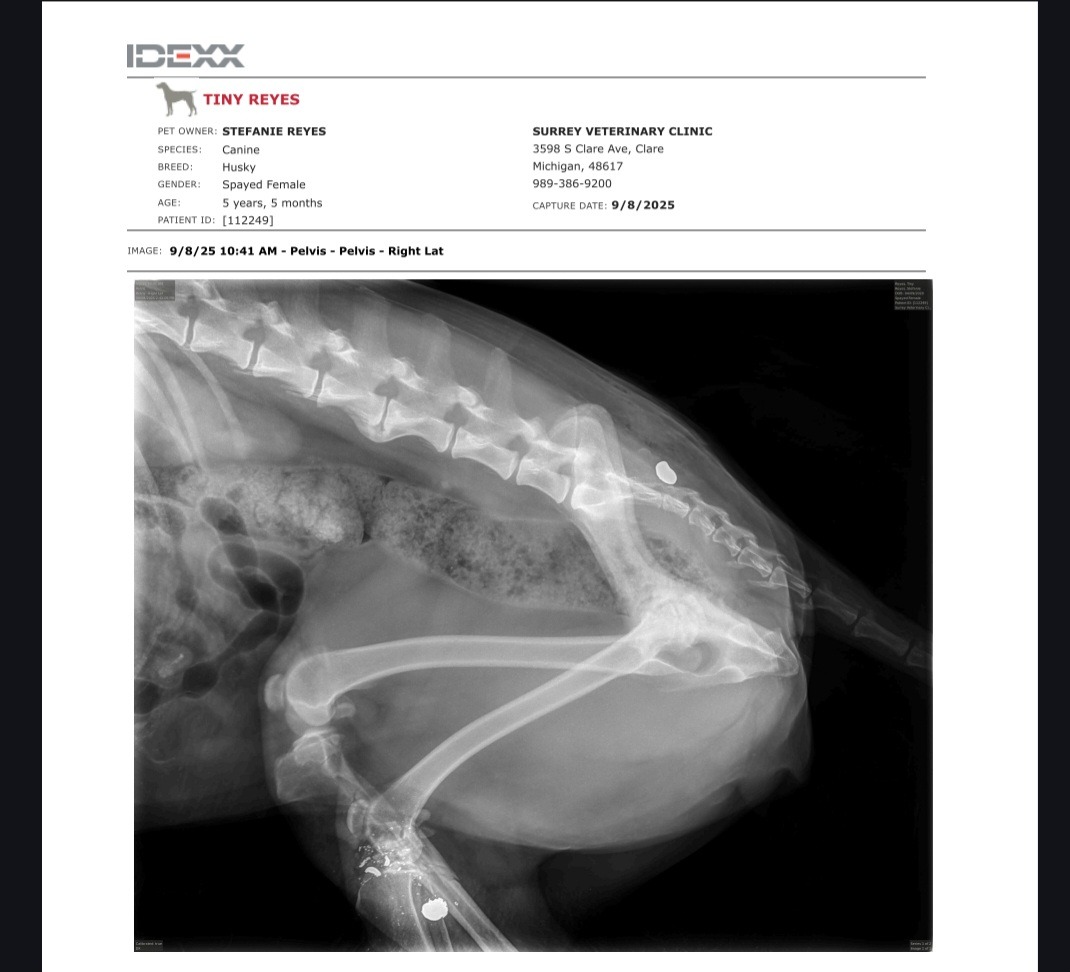

One of the bullets shattered her leg so badly that it can’t be casted. A surgeon at Surrey Vet in Clare, wanted to try saving her leg with a special metal external device. I had several discussions with the staff at Surrey over the last couple days conserning the risks involved, healing process, and the fail rate of this device. I took her to another vet today for a second opinion and after a long discussion about infection rates and fail rates we have decided to move care to M20 Animal Hospital in Midland as they are better equipt to handle this trauma than Surrey. My husband is just weeks away from a seasonal layoff, so our finances are very tight right now. We don’t have a final bill yet, but the surgery is estimated to cost around $2,500.